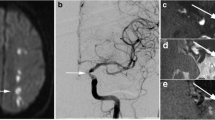

Cross-sectional imaging was performed using a 3 T MR scanner (HDx, GE Healthcare, USA) and an 8-channel phased array brain coil. 3D time-of-flight (TOF) magnetic resonance angiography (MRA) was performed for positioning. Based on the use of MRA, the scan plane was angled to ensure that the cross-sectional images were perpendicular to the diseased section (Fig. 1). Black blood 2D fast spin-echo (FSE) T2-weighted (T2), T1-weighted (T1) and gadolinium-enhanced T1-weighted (CE-T1) images of 12 sections were acquired consecutively. A detailed description can be found in the Supplemental Materials.

MRI images showing an MCA atherosclerotic plaque in a symptomatic patient. A mixture of fresh and chronic infarction involving the right periventricular and frontal subcortical regions was seen in DWI (red dashed curve); the plaque is shown by an arrow in the TOF image, and a cross section at MLA is shown in T2, T1 and CE-T1 images (white arrows: plaque and red asterisks: lumen)

Degree of luminal stenosis was computed from TOF maximum intensity projection (MIP) images following WASID criterion [18]. A plaque was identified if plaque burden [PB = (total wall area - lumen area) / total wall area × 100 %] > 40 %. Lesions with luminal occlusion were identified by using both TOF and T2-weighted images. Lumen and outer wall boundaries were manually segmented in each MR image in which plaque was present using CMRTools (CVIS, UK) (Fig. 2). Minimal luminal area (MLA), PB, plaque volume (PV) and plaque length (PL) were computed based on the segmentation. For those with luminal occlusion, stenosis was 100 %, MLA 0 mm2 and PB 100 %. MR signal intensity may vary within individuals due to factors such as coil positioning. Normalized signal intensity to adjacent grey matter in T1, T2 and CE-T1 images were therefore used for analyses (Fig. 2).

MCA atherosclerosis was observed in 112 patients (72.7 %) in the symptomatic cohort, 26 of which had bilateral lesions (Fig. 3). MCA atherosclerosis was found in 27 volunteers (24.8 %) with none having bilateral lesions. Of all 165 lesions, 152 (92.1 %) were located in M1 section and 13 (7.9 %) in proximal M2 section. In the symptomatic cohort with atherosclerosis, six (5.4 %) patients suffered from transient ischemic attack (TIA) and 106 (94.6 %) from a stroke. Eighty-two (73.2 %) patients showed DWI-positive infarction, with the majority (n = 56) having predominantly subcortical infarcts, nine pial territory infarcts with or without insular infarcts, ten cortical border-zone infarcts, and seven isolated small subcortical infarcts. Seventy-two patients had either acute or acute/chronic infarctions, while only ten had chronic infarctions. Five TIA patients had normal DWI and apart from these five patients, 17 with DWI-negative showed mild ischemic perfusion changes on ipsilateral MCA territory, i.e., increased time to peak, characterized by CTP. In the asymptomatic cohort, only one had evidence of chronic infarction.